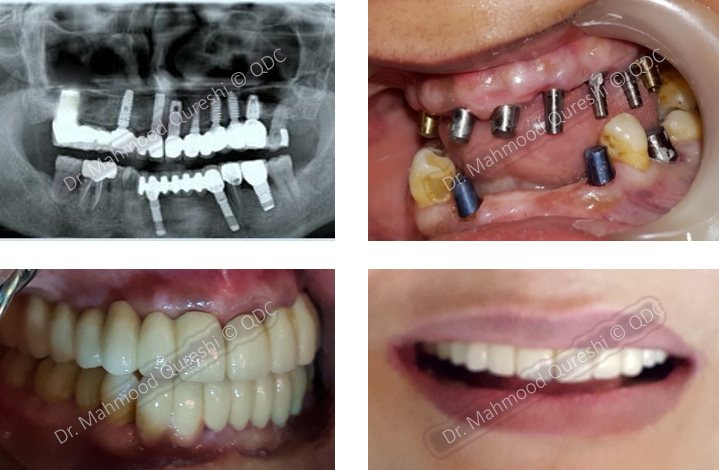

BEFORE

AFTER